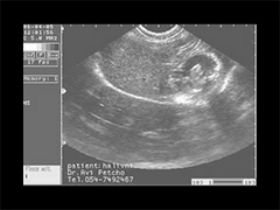

עובר כלב בן 6 שבועות כפי שהוא נראה באולטראסאונד. הקיווקווים הם הצלעות ב"חתך". ניתן להבחין בבועית הקיבה ובית החזה